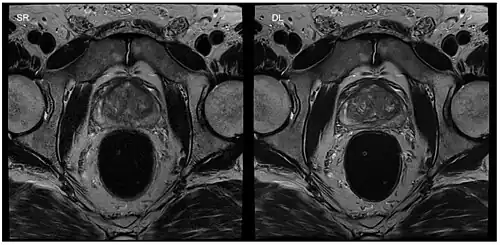

Image reconstruction in RT-MRI benefits from machine learning (ML) or deep learning (DL). A nonlinear kernel, or mapping function, can be developed from the ACS to fill in k-space data and generate the final image.[37] This process as a whole significantly accelerates the MRI process. Image segmentation or identification of lesions can be achieved through machine learning. In deep learning, with a convolutional neural network, the mapping function can be specified by the network. ML and DL improve image resolution as well as imaging speed.[37]